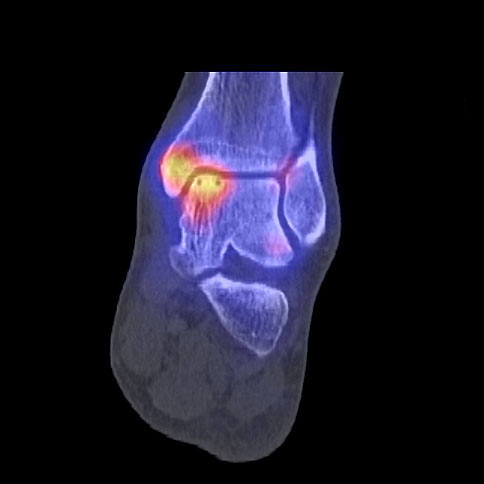

Die Kombination von SPECT und CT in einem Untersuchungsgang bringt wie bereits oben erwähnt eine erhöhte Ortsauflösung und artefaktfreie Darstellung von Knochenstoffwechselveränderungen der SPECT bei gleichzeitig excellent guter anatomischer Darstellung/Zuordnung durch die CT 3. Auf die Vorteile der CT gegenüber dem konventionellen Röntgen muss nicht mehr besonders eingegangen werden. Besonders eignet sich die „SPECT-CT“ zur Diagnostik von Fußerkrankungen (Biersack HJ et al. 2012).

Aufgrund der optimalen funktionellen Darstellung (PET) und der entsprechend guten anatomischen Bildgebung kann dieses kombinierte Untersuchungsverfahren viele Fragestellungen auch im Bereich des Fußes beantworten. Exemplarisch werden folgende Indikationen erwähnt. Abklärung von Infektionen im muskuloskelettalen Bereich 45, Untersuchungen von unklaren Fußschmerzen (Biersack HJ et al. 2012), präoperative Bildgebung beim Charcot-Fuß/diabetischer Fuß 31.